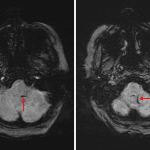

- Focus of restricted diffusion in the dorsal left aspect of the medulla

- Heterogeneous areas of faint restricted diffusion in the left cerebellar hemisphere and left occipital lobe with corresponding patchy T1 signal hyperintensity and susceptibility artifact, more confluent within the left occipital lobe

- T2/FLAIR hyperintensity in the left cerebellar hemisphere extending into the left superior and middle cerebellar peduncles with mild swelling and partial compression of the left lateral margin of the fourth ventricle

- Infarcts with petechial hemorrhage

Small acute/early subacute infarct in the left dorsal aspect of the medulla.

Subacute infarcts in the left cerebellar hemisphere and left occipital lobe with corresponding petechial hemorrhage as well as small hematoma formation in the left occipital lobe. Associated edema and mild mass effect, moreso in the left cerebellar hemisphere with mild mass effect on the fourth ventricle. No evidence of herniation or hydrocephalus.